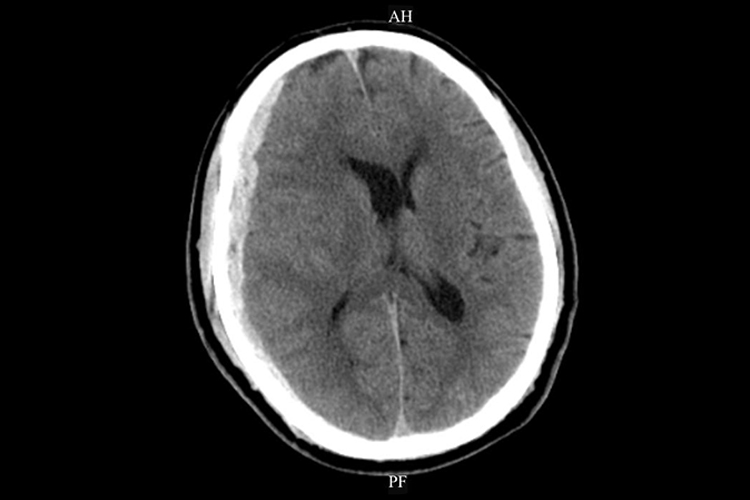

硬膜下血肿ct可见局部有高密度影,少数为等密度、低密度影。

硬膜下血肿的CT影像与发病类型有关,急性硬膜下血肿的CT大多表现为颅板下方的新月形高密度影,亚急性或慢性硬膜下血肿的CT可表现为高密度、等密度、低密度或混杂密度影。此外还常伴随昏迷、头痛、呕吐等症状。